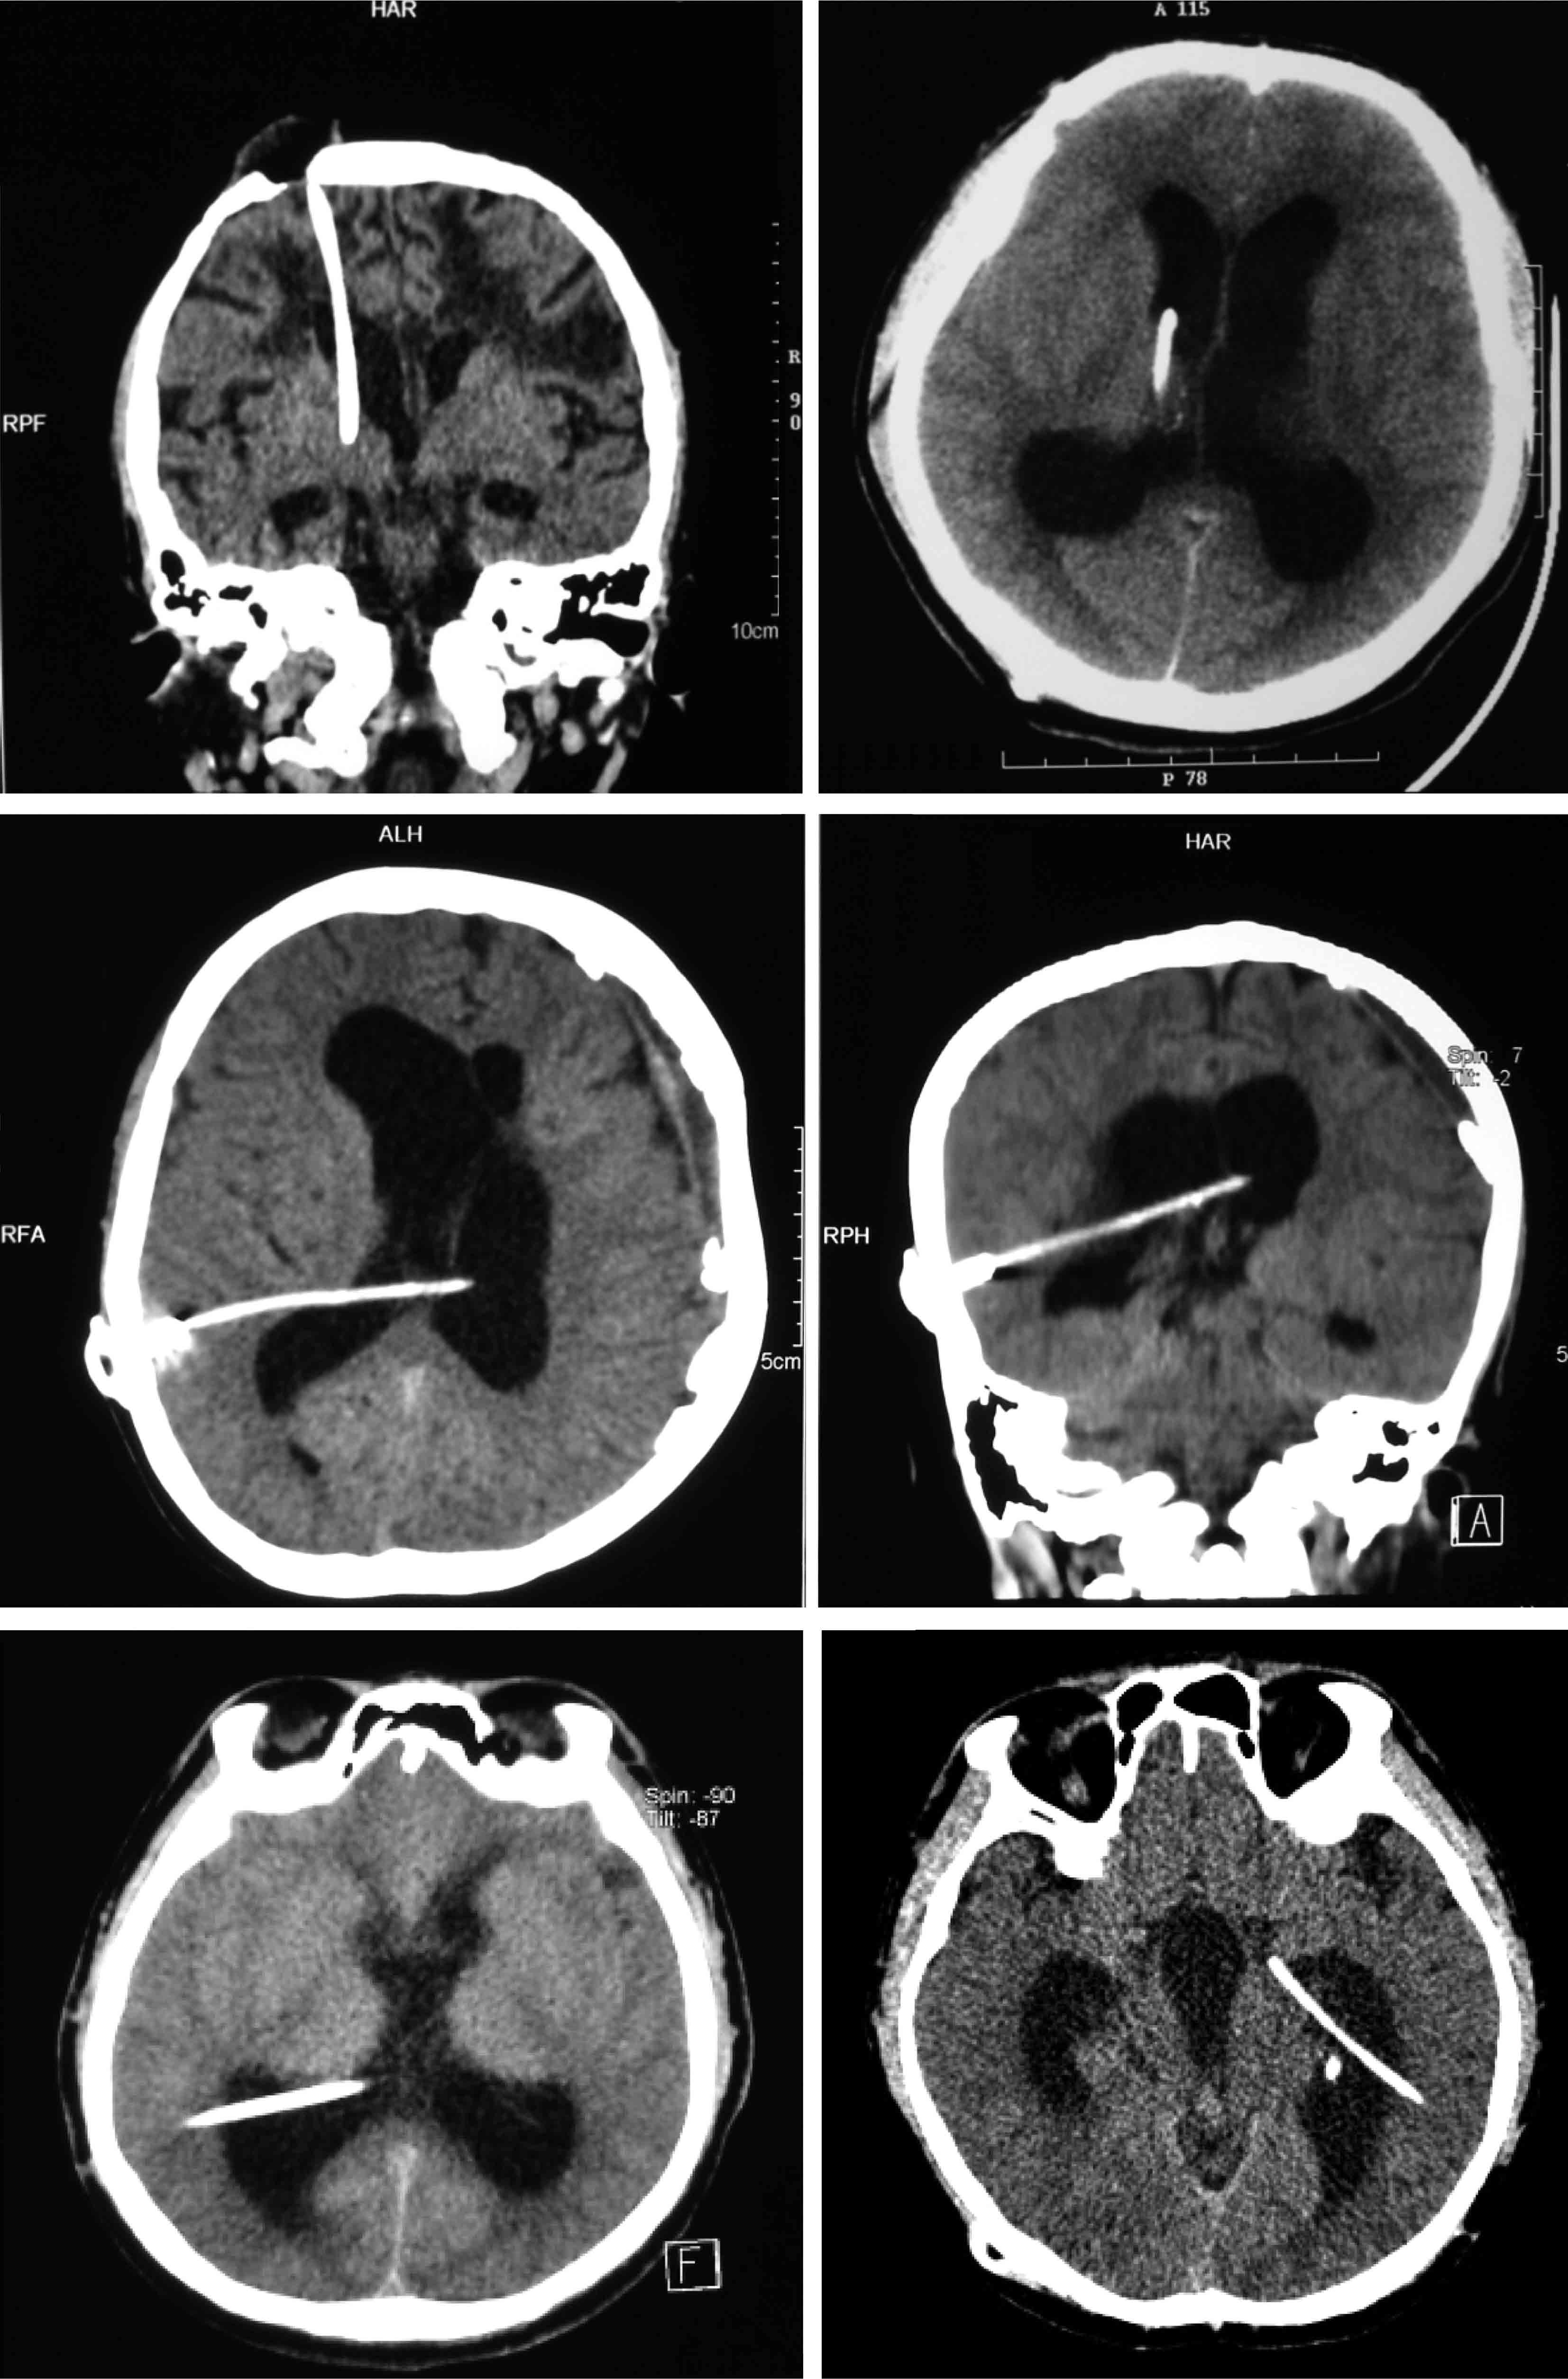

分流管堵塞的防治是脑脊液分流手术的重要技术,其发生常常与分流管位置有关。目前,脑脊液分流手术操作方法多种多样(图3-1-4-1),脑室分流管理想的位置在额角中央略偏向中线(图3-1-4-2),额角没有脉络丛,置于额角中央偏向中线,目的是分流起效脑室缩小后仍能让分流管处于中央位置,减少分流管被脉络丛包裹堵塞的概率(图3-1-4-3)。枕角穿刺置入分流管脑室端,分流管容易被脉络丛包裹(图3-1-4-4)。另外,还有许多分流手术相关并发症(图 3-1-4-5)。

图3-1-4-1 多样的脑脊液分流手术切口

图3-1-4-2 脑室分流管的理想位置

a.CT矢状位见分流管位于侧脑室额角;b.CT冠状位见分流管位于额角略偏向中线;c.内镜下见分流管远端位于室间孔

图3-1-4-3 脑室分流管位置不当导致

图3-1-4-4 枕角穿刺置管后分流管近

a.CT矢状位片所见分流管;b.分流管近端侧孔被脉络丛包裹;c.分流管远端

图3-1-4-5 分流系统故障

a.接头断裂;b.分流管外露;c.分流管自腹壁穿出;d.腹腔分流管进入肠腔,管内充满粪便